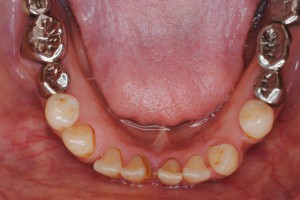

初診 下顎の歯並びの状態

舌体のサイドに歯の痕がくっきりとついている場合は、舌が大きい場合もありますが、下あごの小・大臼歯が内側に倒れて歯列の幅が狭くなっている場合も多いのです。さらには個々の小・大臼歯が上から常に舌に押され続けることで前方に倒されてしまって、前歯にしわ寄せがきて歯並びが乱れることが考えられます。(左下図の白矢印)